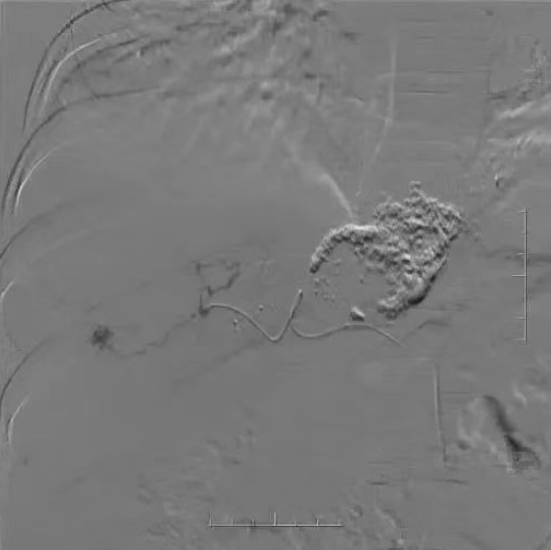

术中造影及栓塞

.png)